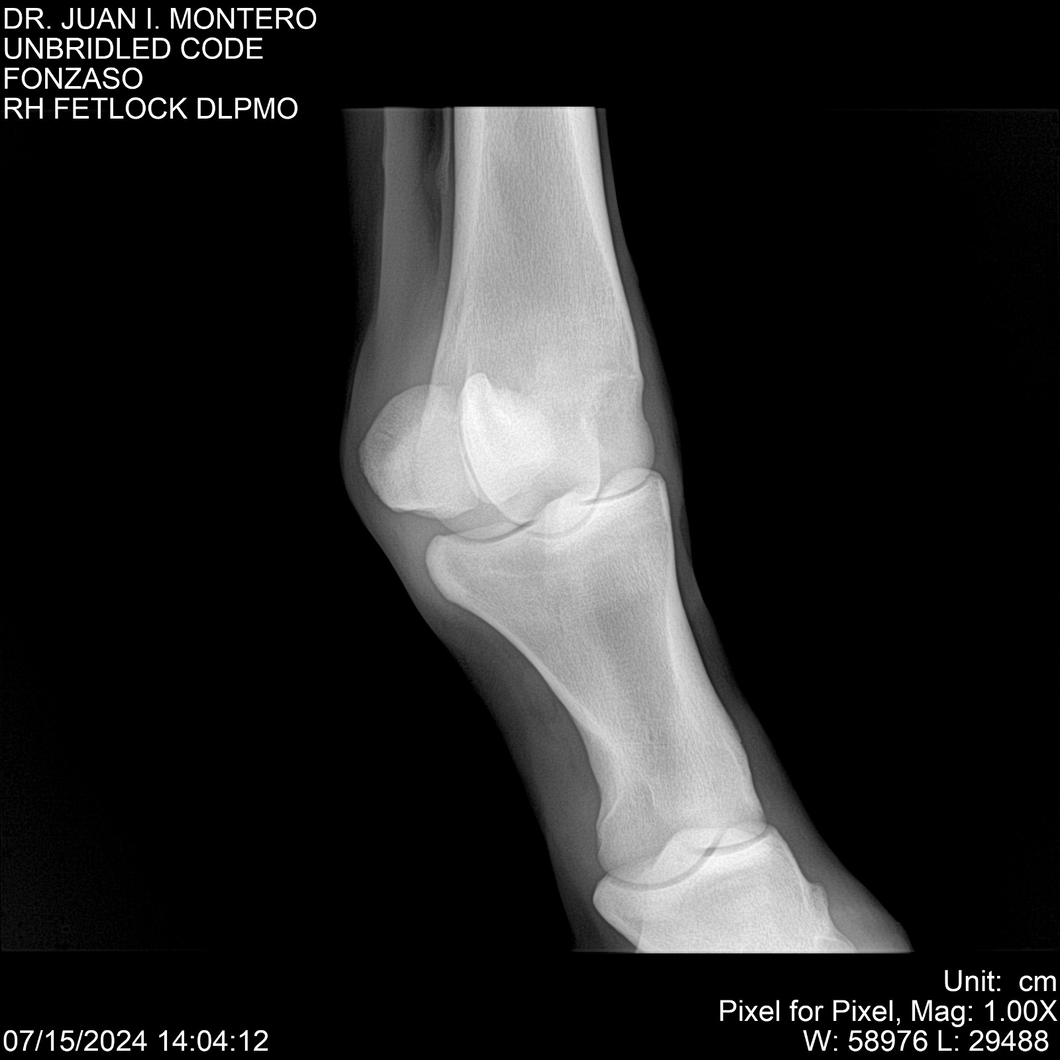

• Empresa: Abelenda N. R., Walter Hugo